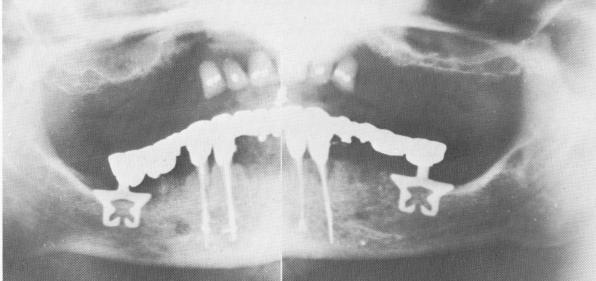

Fig. 13-38. A, A lateral plate roentgenogram shows another case of anterior endodontic root stabilizers in combination with vent-plants and a posterior triplant. B, A Panorex showing four stabilized anterior teeth working in symbiosis with two posterior blades, all of which support a full arch restoration.

1 Endodontic root stabilizers with ventplants & posterior triplant

2 Full arch restoration on stabilized anterior teeth & posterior blades